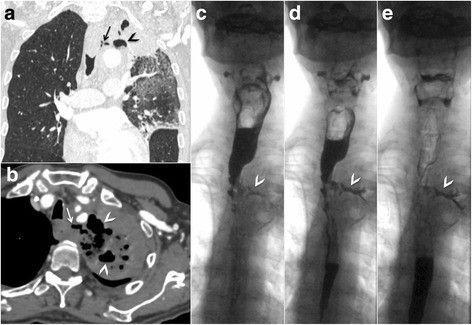

Дисфагия - нарушение глотания пищи. Этот симптом наблюдается более чем у 75 % больных раком пищевода.

Классификация дисфагии по А. И. Савицкому:

1. степень - затруднение прохождения твердой пищи по пищеводу (хлеб, мясо);

2. степень - затруднения, возникающие при приеме кашицеобразной и полужидкой пищи (каши, пюре);

3. степень - затруднения при глотании жидкостей;

4 степень - полная непроходимость пищевода.